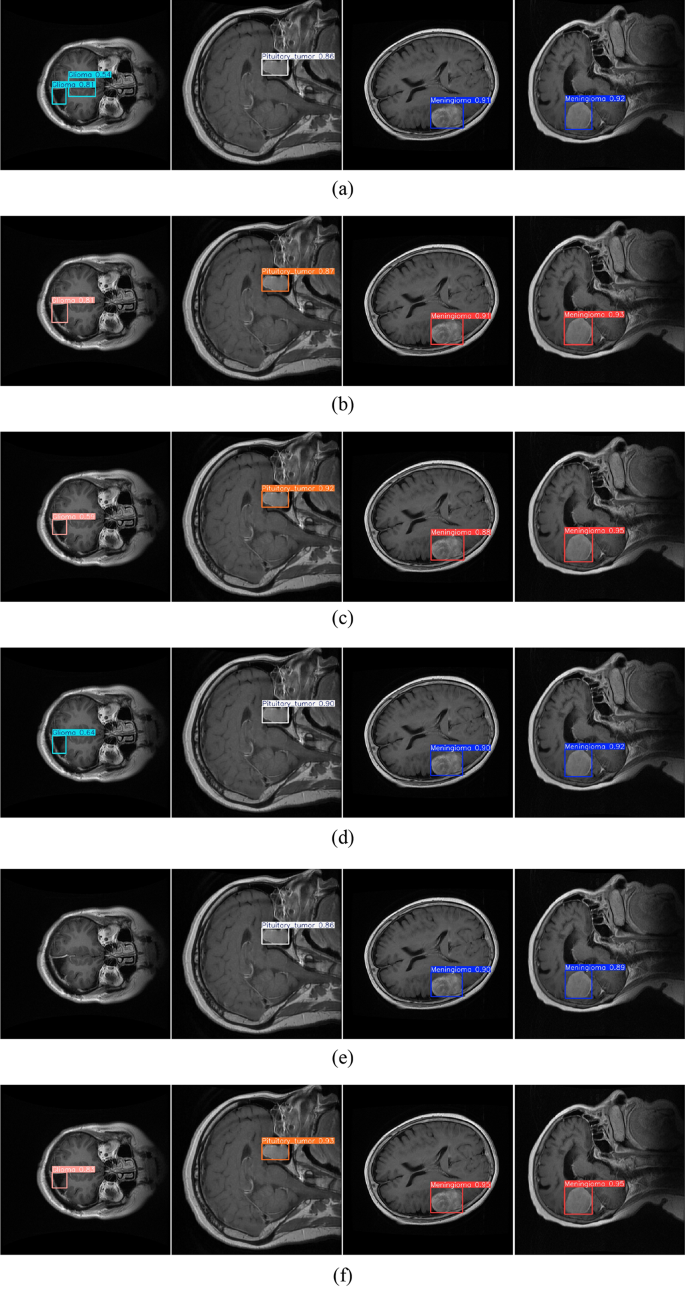

To provide a more intuitive evaluation of model performance in brain tumor detection, a visual comparison of detection results on MRI images was carried out using RT-DETR-r18, YOLOv8n, YOLOv10n, YOLOv11n, YOLOv12n, and the proposed method. In contrast to using numerical metrics alone, the visual results more clearly reveal differences in tumor localization accuracy, confidence levels, and boundary delineation. These visual comparisons enable a more comprehensive and interpretable assessment of the detection capability of each model and offer stronger evidence for their potential applicability in clinical practice.

Figure 11 presents the visual detection results of multiple models on brain MRI images, revealing pronounced differences in detection accuracy and stability. For RT-DETR-r18, overlapping bounding boxes appear in the detection of Glioma, indicating redundancy and instability in lesion boundary localization. Its confidence scores reach 0.86 for Pituitary_Tumor and only 0.91 and 0.92 for Meningioma, reflecting limited overall reliability. YOLOv8n produces cleaner and more stable results, achieving relatively accurate recognition of Glioma (0.81), Pituitary_Tumor, and Meningioma, and demonstrating greater consistency compared with RT-DETR. However, YOLOv10n exhibits reduced accuracy for Glioma (0.59), despite satisfactory outcomes for Pituitary_Tumor (0.92) and Meningioma (0.88, 0.95). YOLOv11n shows marginal improvement for Glioma (0.64) and achieves confidence scores of 0.90 and 0.92 for Pituitary_Tumor and Meningioma, respectively, though inter-category imbalance remains evident. In contrast, YOLOv12n performs notably worse: it fails to detect some Glioma cases, and its confidence scores for Pituitary_Tumor and Meningioma are limited to 0.86, 0.89, and 0.90, all lower than those of earlier models. By comparison, the proposed method demonstrates clear superiority across all three tumor categories. For Glioma, it achieves a confidence score of 0.83, significantly outperforming YOLOv10n, YOLOv11n, and RT-DETR-r18, while effectively eliminating missed detections and redundant bounding boxes. For Pituitary_Tumor, the confidence score rises to 0.93, exceeding all baseline models. For Meningioma, dual detections with 0.95 confidence are observed, producing sharper boundary delineations and highly consistent results. Overall, the proposed approach surpasses existing models in accuracy, stability, and robustness. It not only delivers high-confidence detection results but also markedly enhances performance in challenging categories such as Glioma, demonstrating greater clinical applicability and practical value in medical image detection.